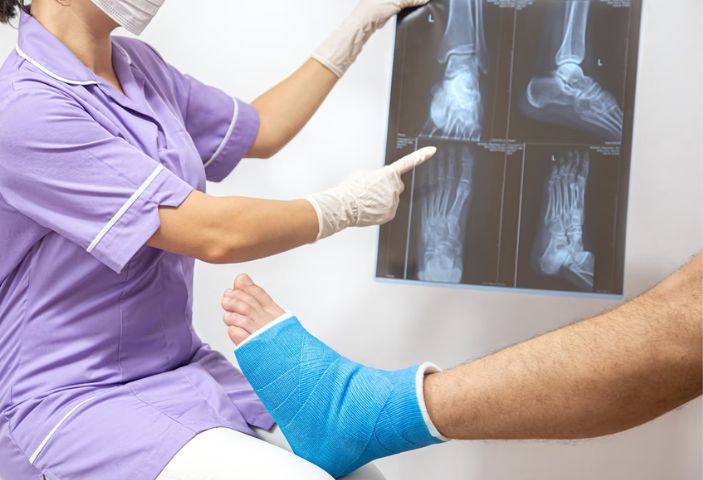

Các biện pháp chẩn đoán gãy xương

Gãy xương được chẩn đoán thông qua các triệu chứng kết hợp kết hợp với thực hiện các xét nghiệm, chẩn đoán hình ảnh.

- Thăm khám lâm sàng: phát hiện triệu chứng điển hình của gãy xương, phân loại gãy xương và đưa ra các chỉ định chẩn đoán hình ảnh tương ứng.

- Thực hiện kỹ thuật chẩn đoán hình ảnh (Xquang, CT, MRI): Phương pháp này tạo ra những hình ảnh hai chiều về xương, giúp bác sĩ xác định rõ các vết gãy, mức độ tổn thương xương, khớp, các cơ quan, phần mềm, mô, gân, cơ, dây chằng… lân cận và đưa ra phương pháp điều trị phù hợp.

- Xét nghiệm sinh hóa, xét nghiệm huyết học: đánh giá nguy cơ mất máu trong gãy xương, tình trạng nhiễm trùng vết thương giúp bác sĩ tiên lượng để có biện pháp điều trị an toàn.